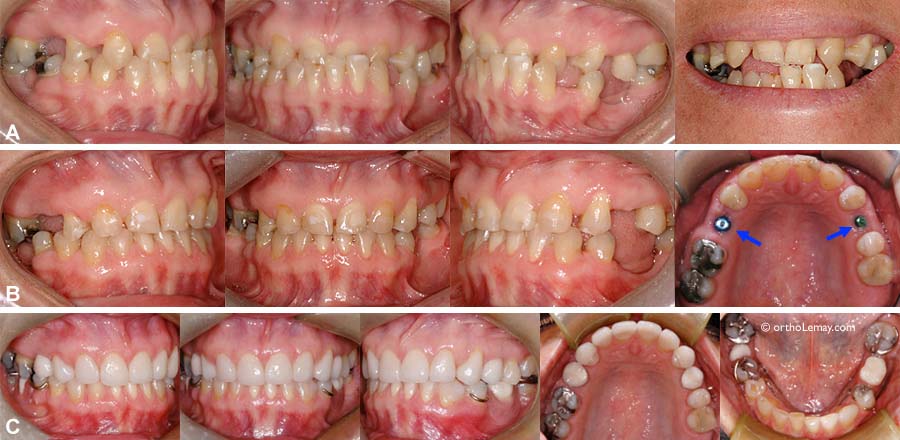

Adulte présentant une dentition “mutilée” (caries, dents fracturée et extraites)

Adulte présentant une dentition “mutilée” (caries, dents fracturée et extraites). L’orthodontie a préparé la dentition pour que le dentiste puisse faire des restaurations adéquates (couronnes et ponts).